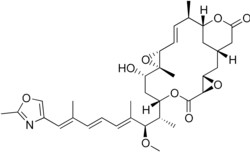

| C35H47NO9 | |

| Molar mass | 625.749 g/mol |

Rhizoxin is a 16-membered lactone ring connected to an oxazole ring by a long unsaturated chain.[8]